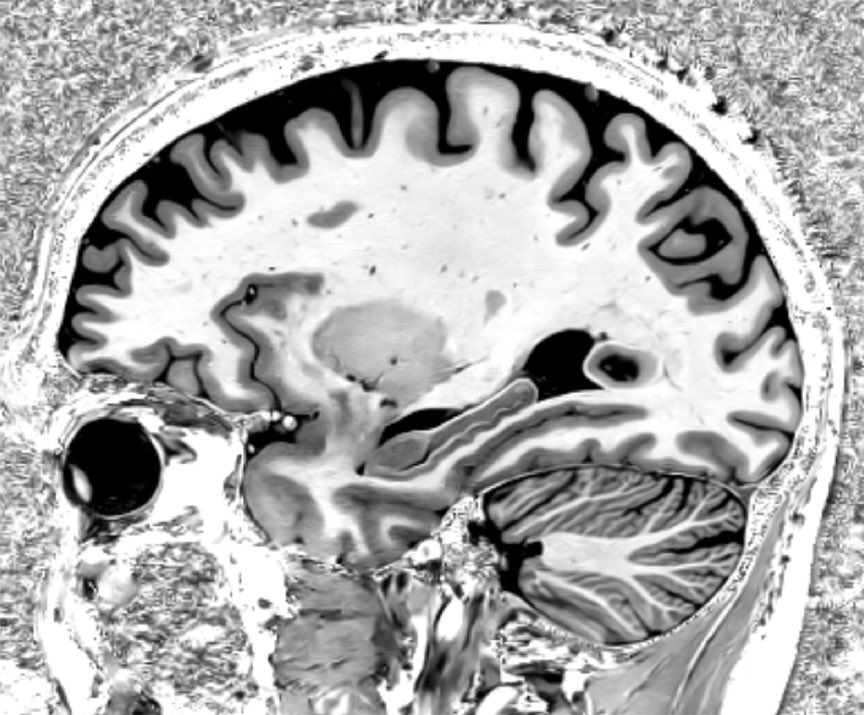

Milestone week for #7T program at #MayoClinicFlorida — we’ve scanned over 4000 clinical patients, including >1000 #epilepsy evals, >900 #MS patients, & many more! We have come so far & helped so many, but only getting started! Many amazing things on the horizon! @MayoRadiology